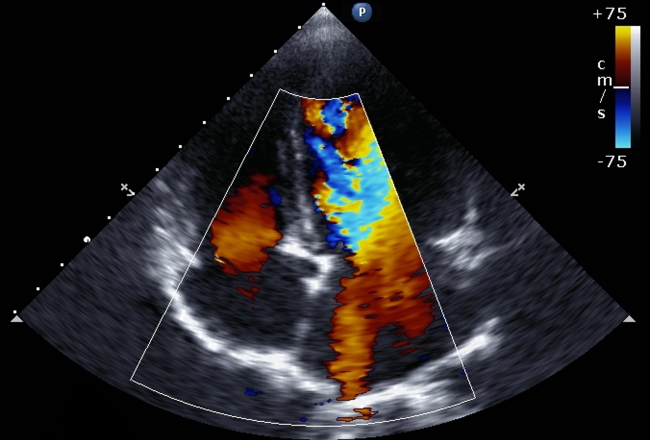

Lançamento do Turing de Ecocardiografia

É com orgulho que anunciamos a disponibilidade imediata do Turing EC, uma versão do Turing específica para exames cardiológicos e o mais novo membro da família. Criado com consultoria de dois experientes médicos cardiologistas, o Turing EC vem com suporte a laudo estruturado de exames de Ecocardiografia e Doppler de Carótidas, e pode ser experimentado gratuitamente neste link. Instale hoje mesmo e conheça.